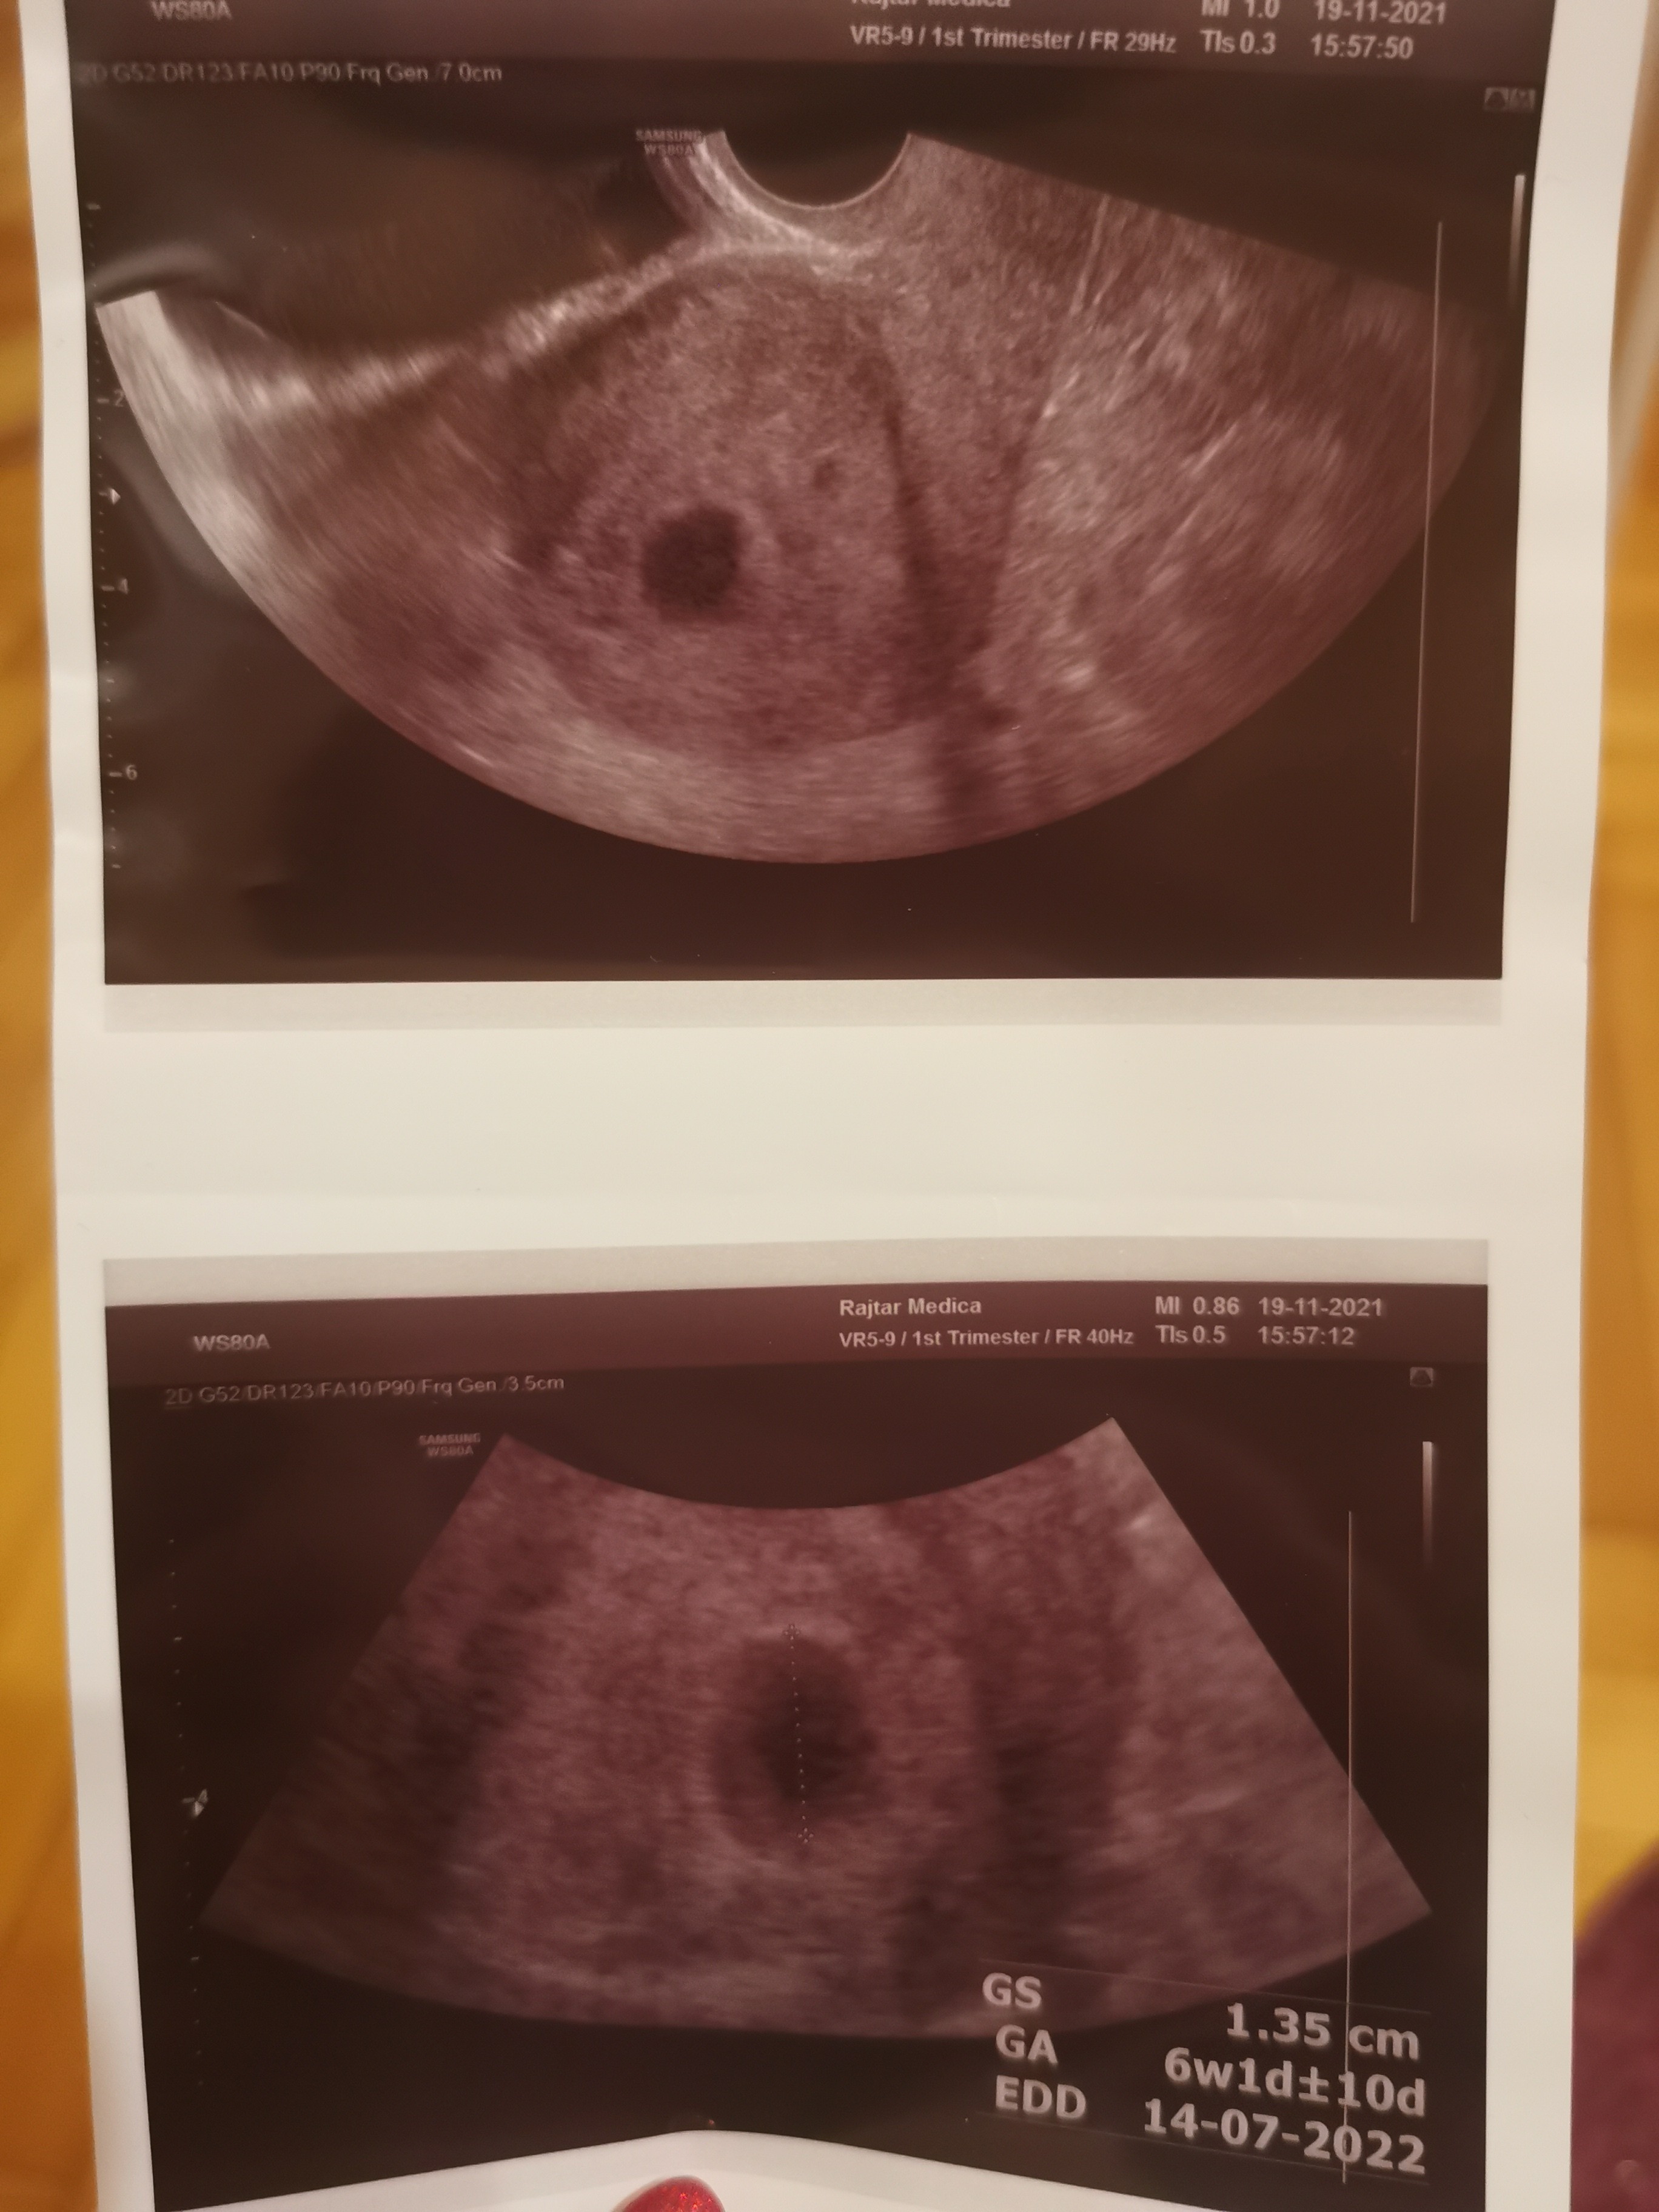

W czerwcu byłam w identycznej sytuacji. W 5+3 w badaniu usg sam pęcherzyk ciążowy. Tydzień później krwawienie i szpital okazało się, że brak jest zarodka. Wypisałam się ze szpitala i kilka dni później wizyta u mojego ginekologa, niestety od szpitala niewiele się zmieniło, brak zarodka. Robiłam bete kilka razy i przyrost miałam prawidłowy, ostatni pomiar w 7 tc beta na poziomie 90000. Po trzecim badaniu usg przestałam się oszukiwać, pogodziłam się z sytuacją i oczekiwałam na poronienie aż do 11 tc (przez wysoką betę która stale rosła).

Jeśli u Ciebie lekarz nie zobaczył w pęcherzyku ciążowym pęcherzyka żółtkowego, to bardzo mi przykro, ale to puste jajo płodowe.